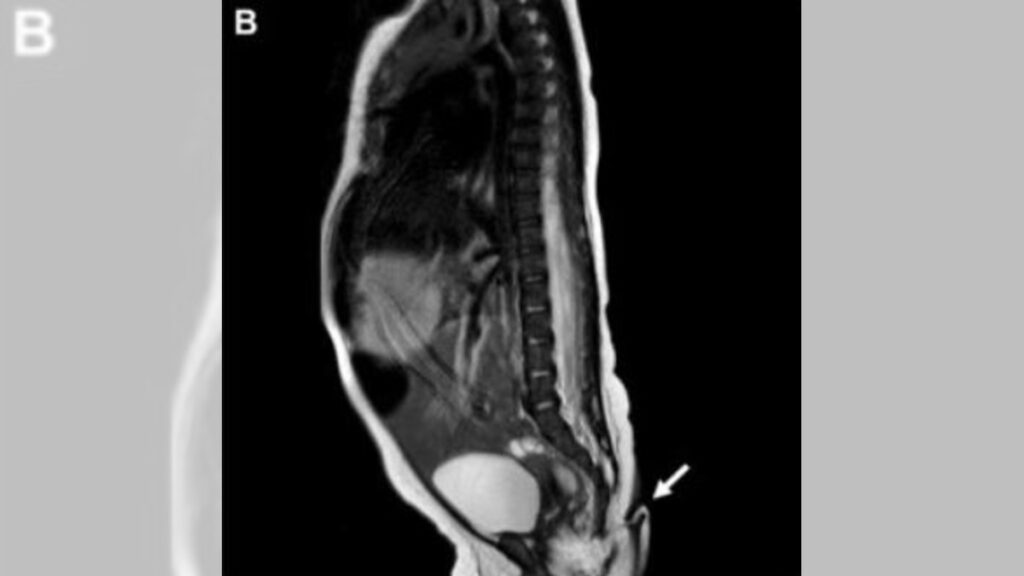

Fue hasta que estuvo fuera del vientre de su madre que los doctores detectaron que la recién nacida presentaba una estructura en forma de cola de 5.7 cm de longitud y de entre 3 y 5 mm de diámetro. La extremidad se encontraba en la hendidura interglútea.

Detalla que la estructura de la cola era blanda, cubierta de piel y pelo fino, se podía mover pasivamente sin dolor, pero no mostraba ningún movimiento espontáneo. Al detectarlo, los médicos procedieron a pellizcar la extremidad con una aguja, al hacerlo la bebe lloró, por lo que confirmaron conexión nerviosa.

Tras cumplir los dos meses, la menor fue revaluada por el equipo de pediatría y cirugía general, encontraron que la cola había crecido 0.8 centímetros, por lo que fue extirpada y la zona afectada fue reconstruida mediante plastia de Limberg.

Una vez separada del cuerpo de la bebé, la cola fue sometida a más análisis en los que se reveló que la muestra contenía tejido blando, incluyendo tejido fibroadiposo, estructuras vasculares y haces nerviosos, cubiertos por piel, sin alteraciones histopatológicas.